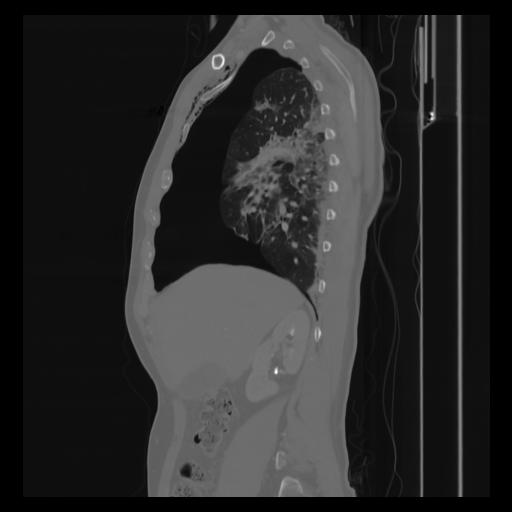

30 CUERPO,CE,Sagittal,3.000,CUERPO,Sagittal,